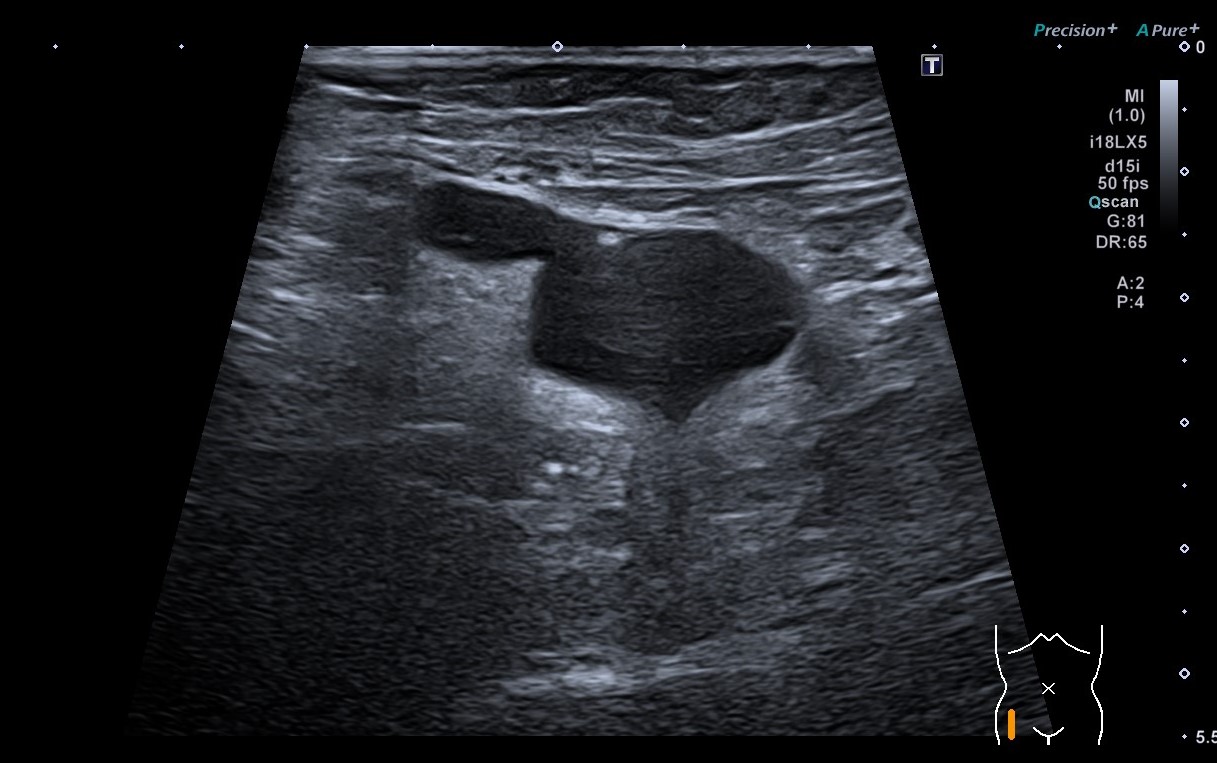

Se aprecia una colección líquida de unos 30 milímetros (mm) alargada con el extremo distal que termina en forma de pico en región inguinal derecha. Ecográficamente se aprecia ligera modificación con Valsalva.

Semanas después se realiza ecografía reglada por el radiólogo que describe una colección de unos 33 mm con morfología «en pico», que se modifica discretamente con Valsalva presentando un cuello de unos 7 mm. Impresiona de imagen compatible con una hernia inguinal con contenido líquido aunque su morfología peculiar recuerda al quiste de Nuck, que resulta excepcional en el rango de edad de la paciente.